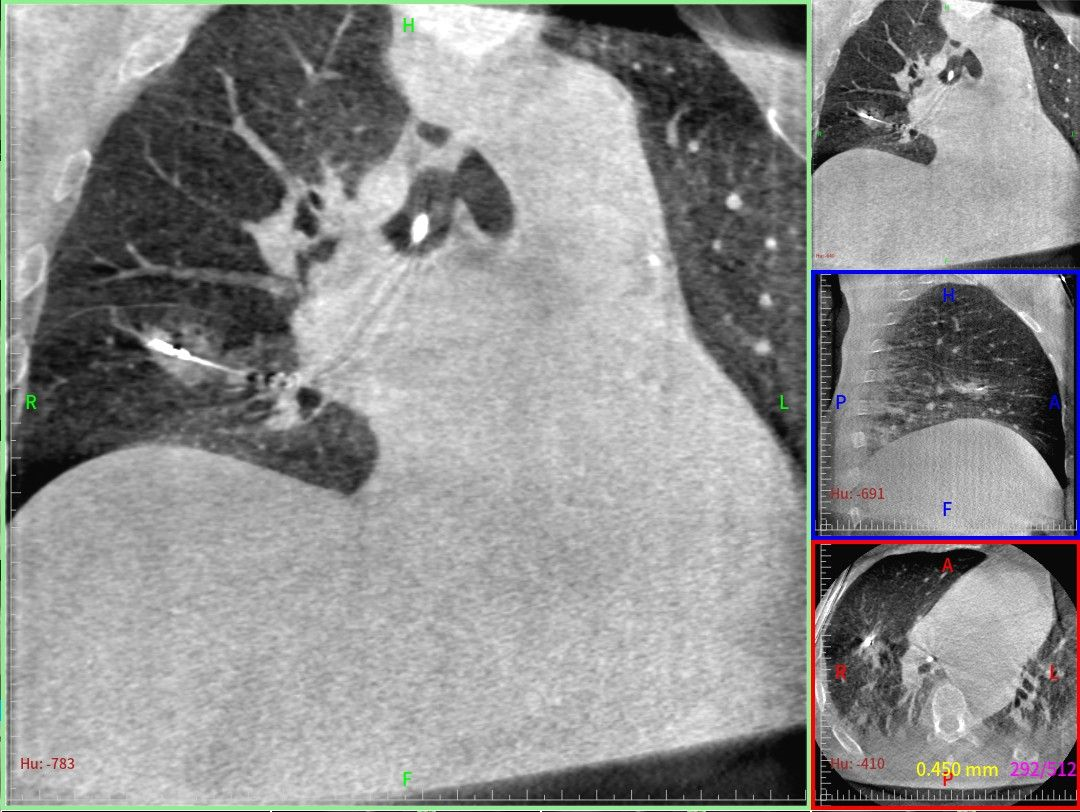

该名患者是一位67岁男性,既往有慢性阻塞性肺疾病病史,左肺上叶腺癌术后2个月时,发现右肺中叶出现混合密度磨玻璃结节,病灶大小为17×12毫米,PET-CT检查提示结节性质为恶性。经过多学科会诊(MDT)研讨,考虑患者前期已接受左肺上叶切除术,且基础肺功能较差,最终为其制定了超微创经导航支气管镜右肺中叶外侧段肺高危结节活检及冷冻消融术的治疗方案。

王峰教授凭借丰富的手术经验,术前为患者制定了详细的柔性导航支气管镜机器人系统协同冷冻消融的治疗方案。术中,O臂CT精准定位病灶,全程监测导管位置与冷冻消融区域。在导航支气管镜机器人系统三维实景的“指引”下,王峰教授沉稳地操控手柄,驱动支气管镜机器人精准到达右肺中叶的目标病灶。现场细胞学检测发现了高度疑诊腺癌的异常细胞。活检完成后,通过支气管镜机器人系统置入冷冻消融探针,借助O臂CT再次校准,随后启动消融治疗。消融范围完美覆盖了病灶,整个手术过程无出血、气胸等并发症发生,取得圆满成功。

术中O型臂三维成像精准确认消融探针及病灶位置